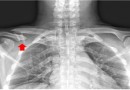

쇄골

쇄골 (정의)쇄골은 흉골과 견갑골을 잇는 긴뼈로 흔히 빗장뼈라고도 하며 팔을 몸통에 고정시켜주는 역할을 합니다. 이 쇄골 뼈가 외상으로 인해 부러지거나 깨지는 것을 쇄골 골절이라고 합니다. 쇄골 골절은 골절 부위 양쪽 뼈의 전위는 심하지 않고 주위 조직의 손상 없이 쇄…